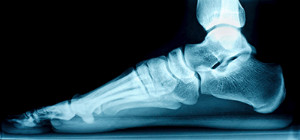

The medical term for flat feet is known as pes planus or pes valgus. The noticeable symptom of flat feet is a lack of an arch when the foot is lying flat on the ground. Most babies are born with flat feet and the arch typically develops with age. Research has indicated there are two types of flat feet. An arch that can be seen when the foot is elevated is known as a flexible flat foot and an absent arch also when the foot is elevated is known as a rigid flat foot. Flexible flat feet generally do not cause severe pain although some patients may feel mild achiness if intensely walking. Abnormal foot development may be the cause of rigid flat foot and surgery can be a necessary option for a significant correction. Some patients will even have a second surgery after the foot has fully formed to fuse the bones together. If you have flat feet, it is advised that you confer with a podiatrist.

Flatfoot is a condition in which the arch of the foot is depressed and the sole of the foot is almost completely in contact with the ground. About 20-30% of the population generally has flat feet because their arches never formed during growth.